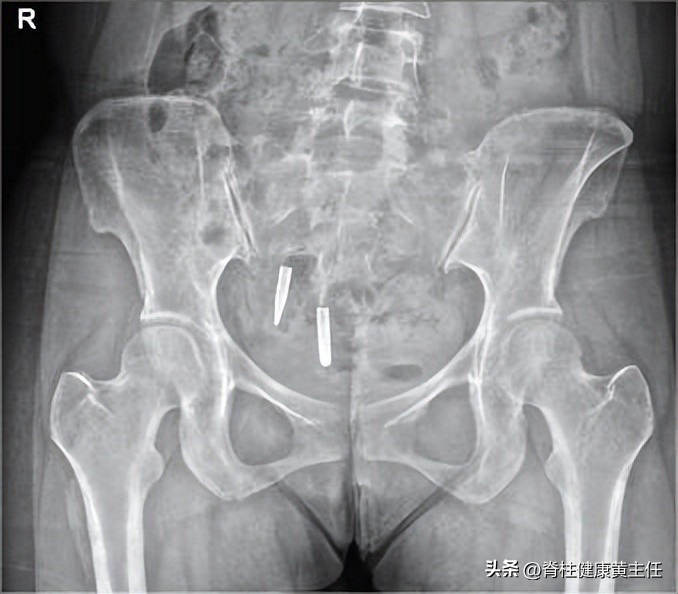

骨盆X光检查

2、X光片检查:腰椎骨盆X光检查示,腰椎多棘突向右偏歪,腰椎生理曲度存在,髂骨右高左低,髂骨右髋左窄。